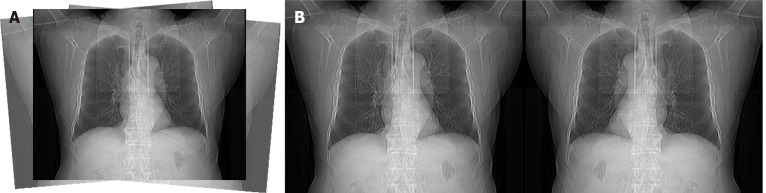

Aim: To develop and evaluate a novel deep learning approach to automate the determination of CCTA scan ranges using anteroposterior scout images.

Methods: A retrospective analysis was conducted on chest CT data from 1388 patients at the Radiology Department of the First Affiliated Hospital of a university-affiliated hospital, collected between February 27 and March 27, 2024. A deep learning model was trained on anteroposterior scout images with annotations based on CCTA standards. The dataset was split into training (672 cases), validation (167 cases), and test (167 cases) sets to ensure robust model evaluation.